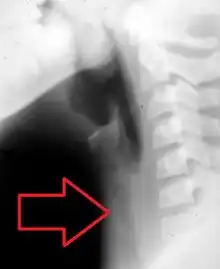

The diagnosis of tracheitis requires the direct vision of exudates or pseudomembranes on the trachea. X-ray findings may include subglottic narrowing. The priority is to secure the patient's airway, and to rule out croup and epiglottitis which may be fatal. Suspicion for tracheitis should be high in cases of onset of airway obstruction that do not respond to racemic epinephrine.